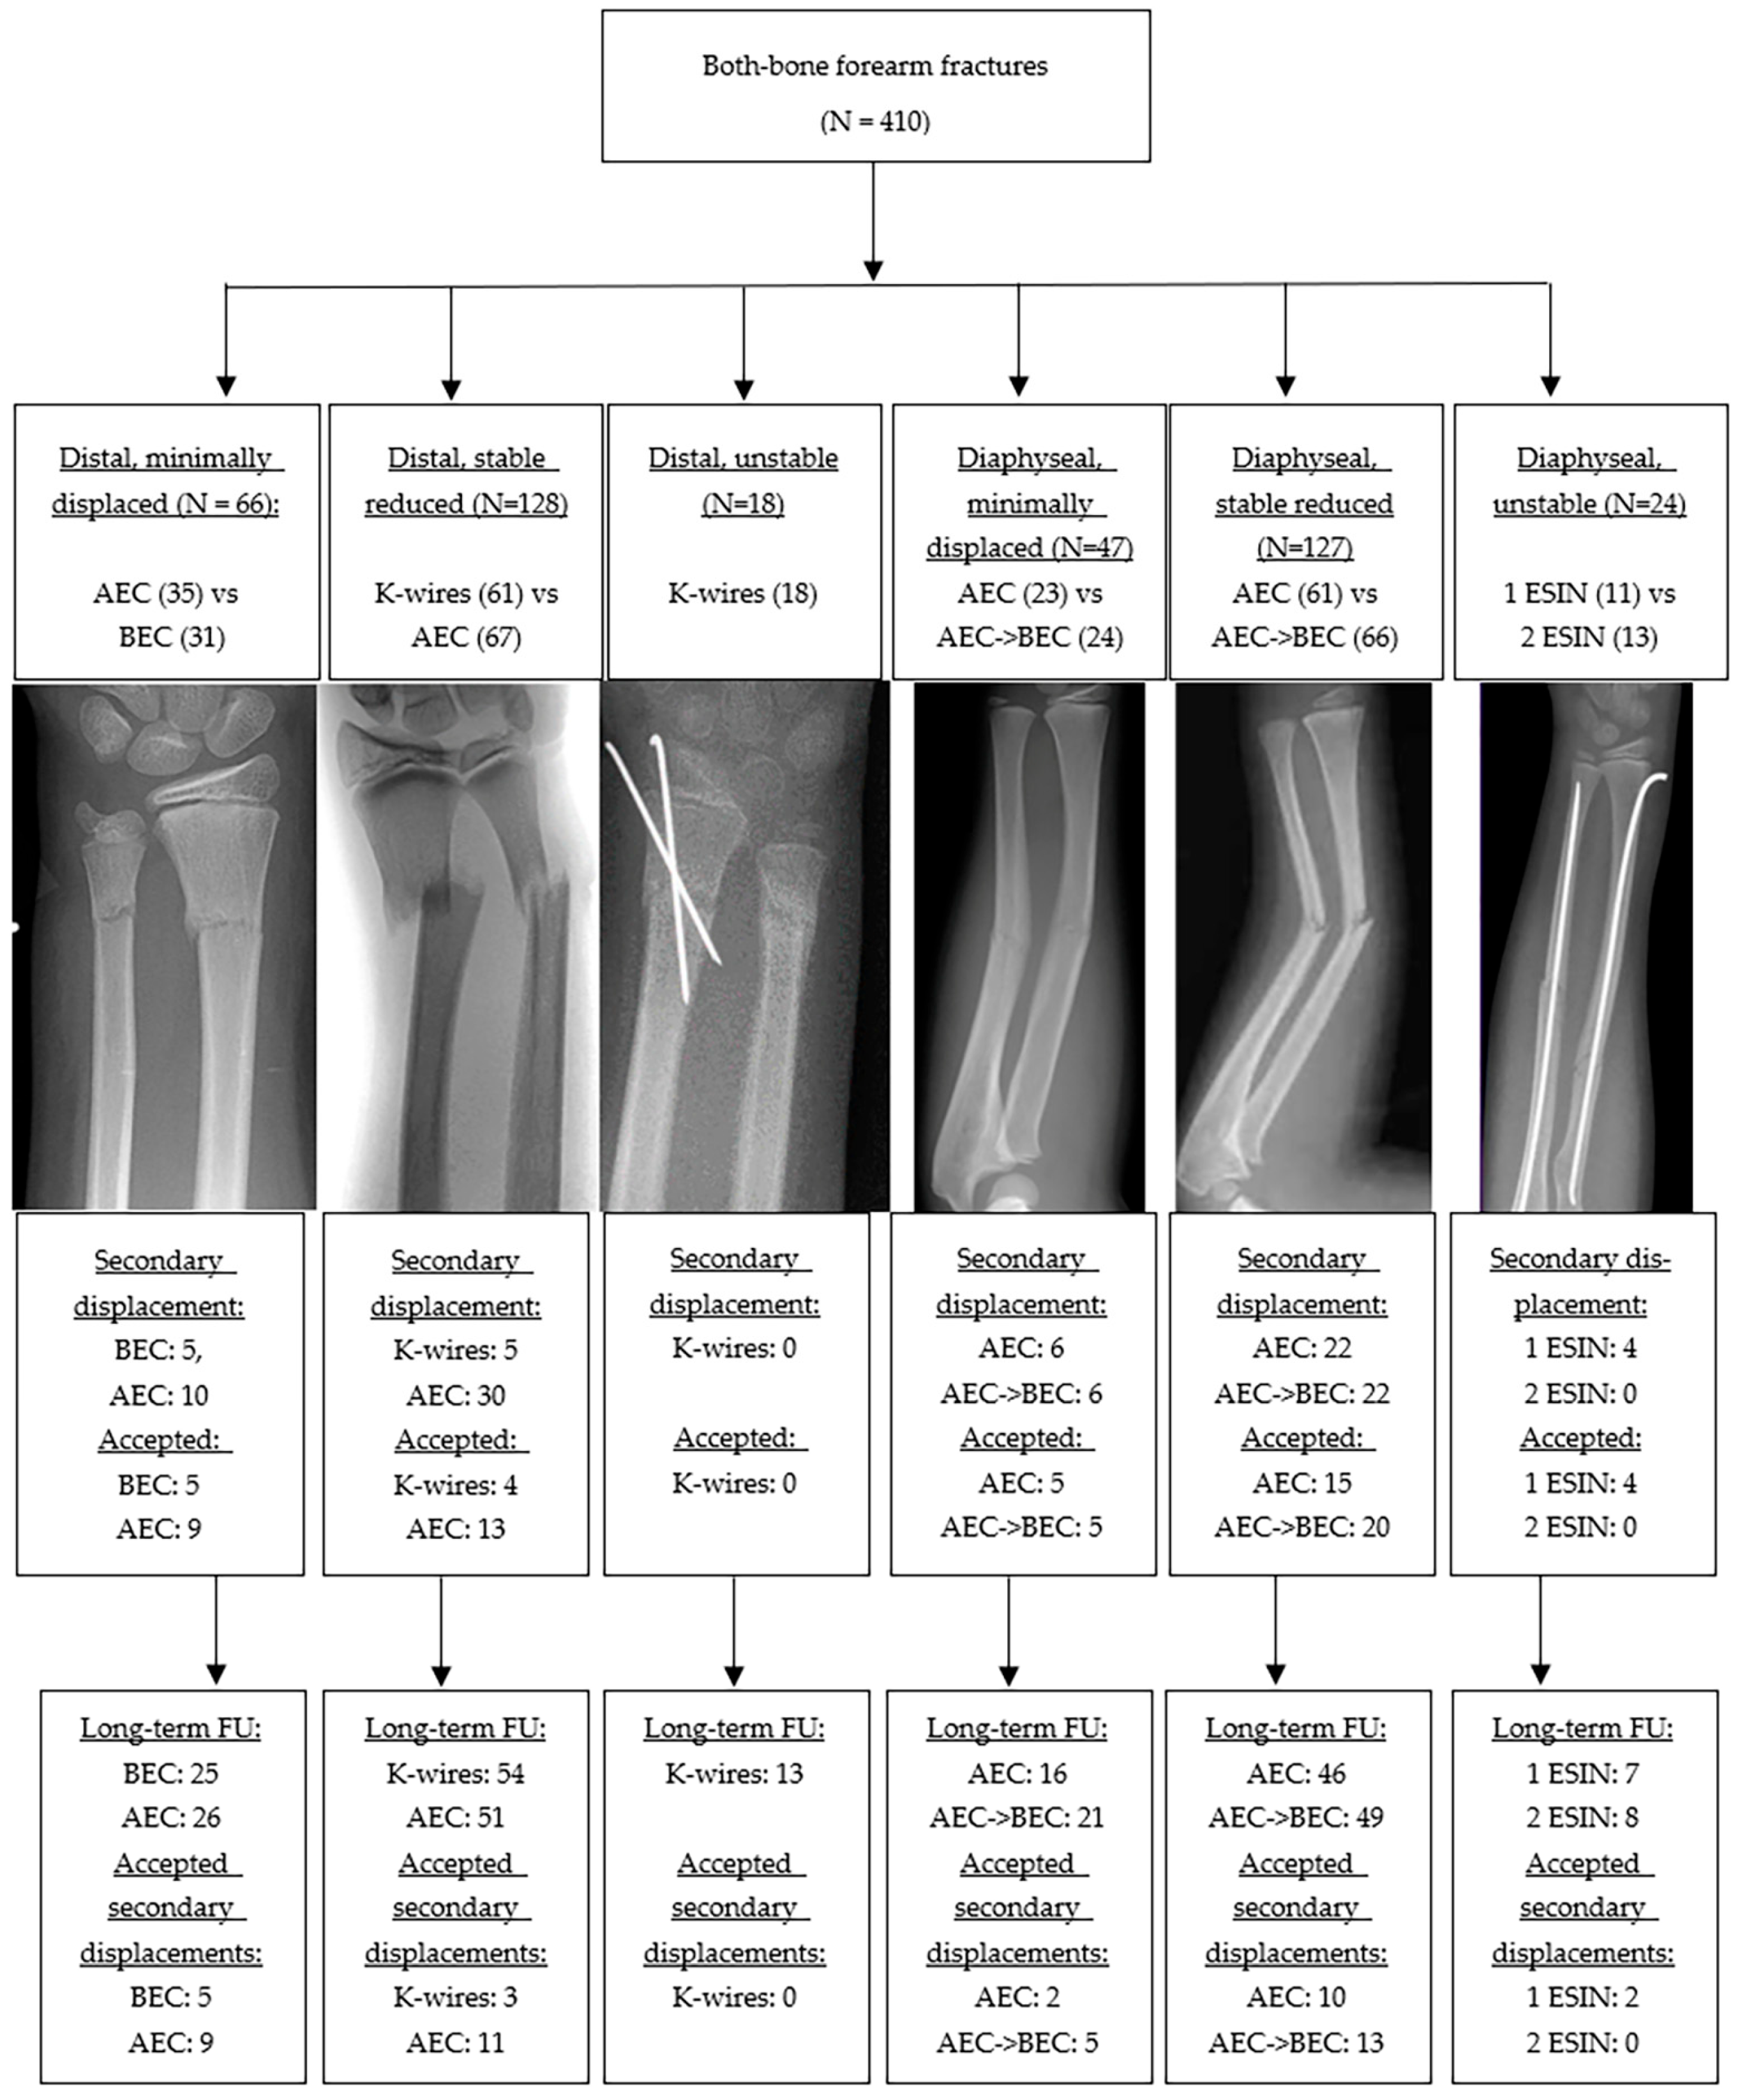

3.1. Participants, Fracture Characteristics and Treatment

3.1.1. Distal Metaphyseal Fractures

3.1.2. Diaphyseal Fractures